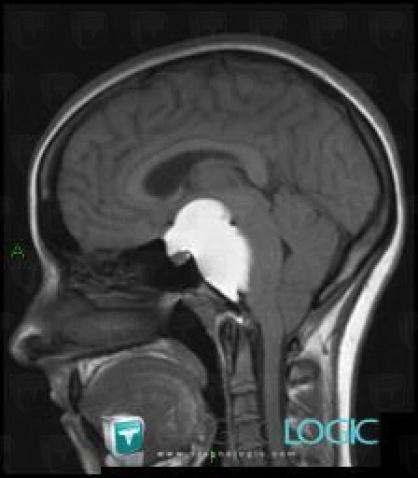

Craniopharyngiome, Espaces peri cérébraux supratentoriels, Hémisphères cérébraux, IRM

Voici les informations spécifiques à l'image clé ci dessus:

- Diagnostic Craniopharyngiome, Localisation(s) Hémisphères cérébraux, comportant les gammes Lésion intracérébrale en hypersignal T1Hypophyse et région parasellaire, comportant les gammes Masse sellaire et parasellaire, Lésion en hypersignal T1 sellaire et parasellaireFaux du cerveau / Ligne médiane, comportant les gammes Masse de la ligne médianeEspaces peri cérébraux supratentoriels, comportant les gammes Lésion extra axiale supra tentorielle